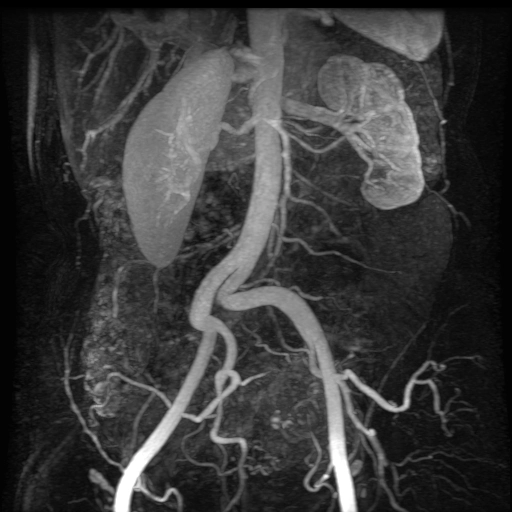

Động mạch thận phụ (Multiple renal arteries)